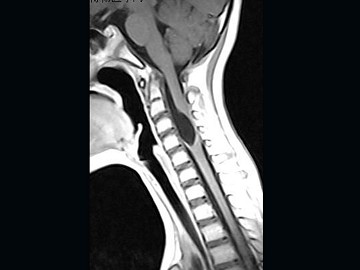

女,9岁,颈部疼痛、活动受限2个月,MRI检查如图,最可能的诊断为()

A.室管膜瘤

B.星形细胞瘤

C.神经鞘瘤

D.髓内囊肿

E.脊膜瘤